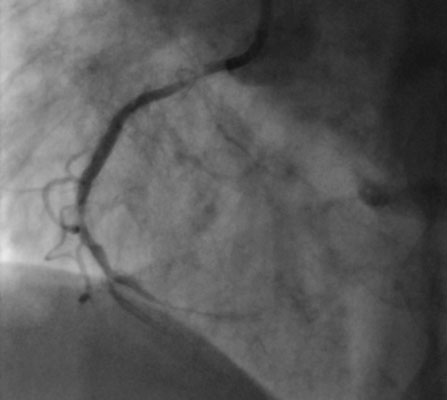

Диагностика: Коронарография, проведенная в ЦЭЛТ, обнажила сложную картину: многососудистое поражение коронарных артерий с обширным отложением кальциевых бляшек по всей венечной системе. Такая степень кальциноза делала стандартную ангиопластику (баллонное расширение сосуда) невозможной.

Под ангиографическим контролем, через ранее установленный доступ в правой лучевой артерии, коронарный проводник направил бур Rotablator в правую коронарную артерию. В зоне кальцинированного поражения, на сверхвысоких оборотах (от 160 до 180 тысяч в минуту), была проведена атерэктомия. Алмазный бур бережно удалил кальциевые отложения со стенок артерии, сохраняя ее эластичность. Это позволило создать необходимое просвет сосуда, подготовив его для последующего стентирования.

На контрольная ангиографии выявлен хороший непосредственный результат в местах ангиопластики с минимальным остаточным стенозом, с отсутствием признаков дессекции (повреждение внутренней стенки сосуда), кровоток по TIMI III. Пациент был выписан на следующий день после операции в удовлетворительном состоянии.